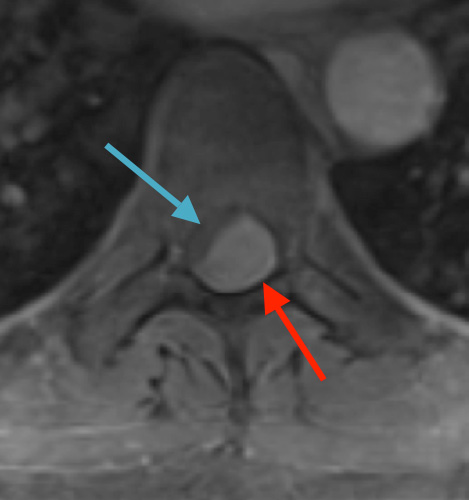

Preoperative MRI T2 demonstrating obstruction of CSF around the cord (blue arrow), resulting from the tumor (red arrow)